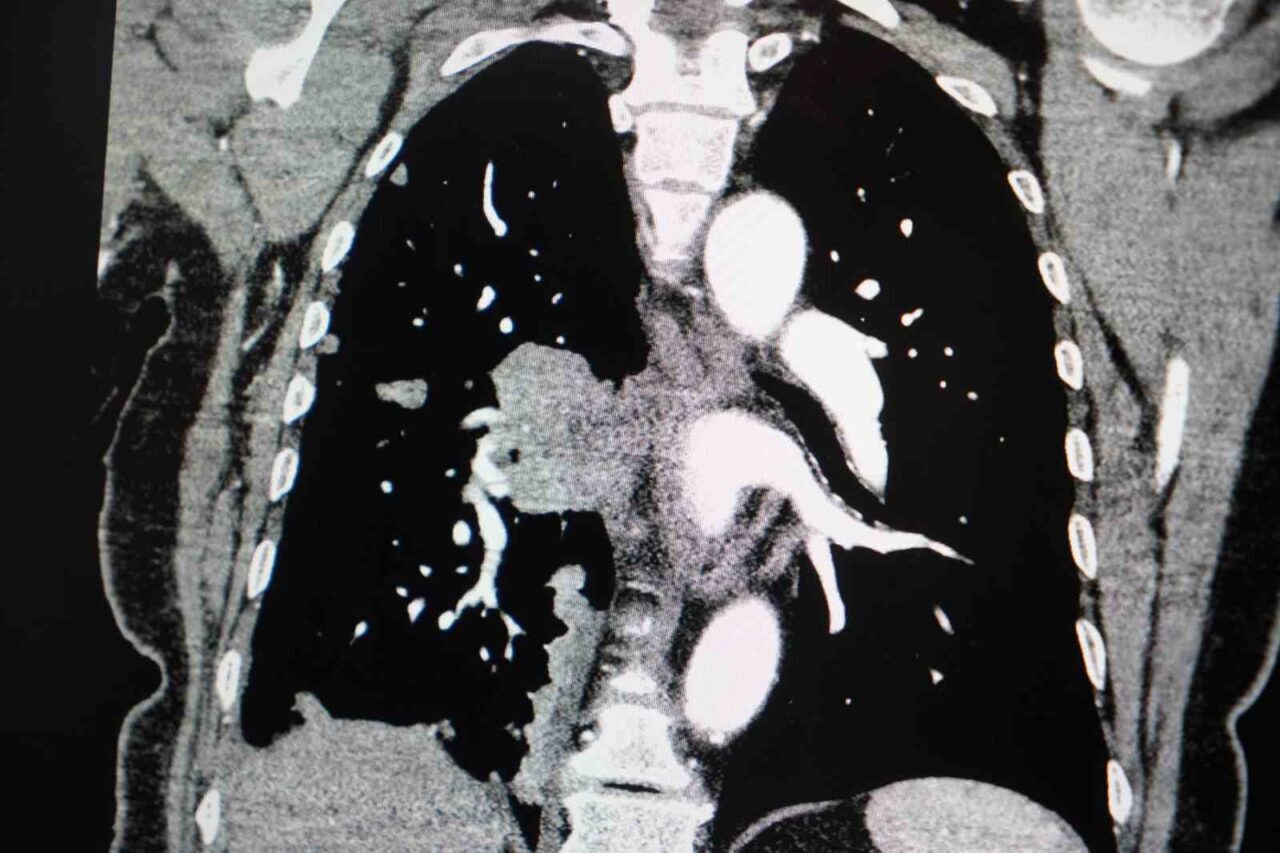

Akciğer kanseri vakalarındaki artışa da dikkat çeken Özkaya, “Son yıllarda hem sigara içen hem de hiç sigara kullanmamış bireylerde akciğer kanseri vakalarında dikkat çekici bir artış görüyoruz. Özellikle kadınlarda adenokarsinom tipi akciğer kanseri belirgin şekilde artış göstermektedir., Yapılan son araştırmalara göre akciğer kanseri teşhislerinin yaklaşık yüzde 20’si hiç sigara içmemiş bireylerde konuluyor. Bunun en önemli nedeni pasif içiciliktir. Yani siz sigara içmeseniz bile, yakın çevrenizde sigara içiliyorsa akciğer kanseri riskiyle karşı karşıya kalabilirsiniz” ifadelerini kullandı.